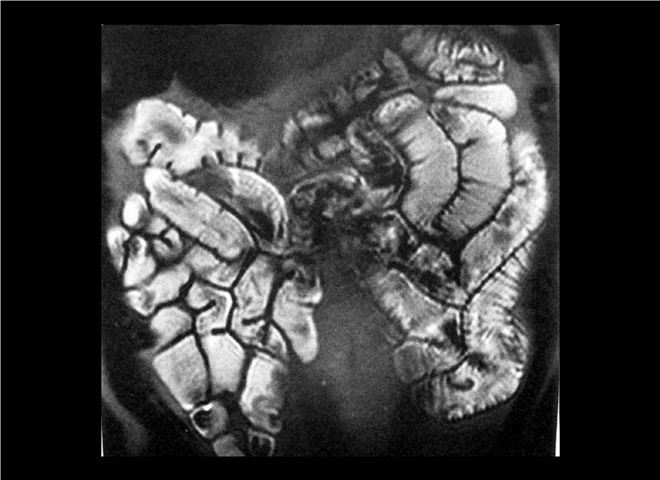

13_CT增强扫描